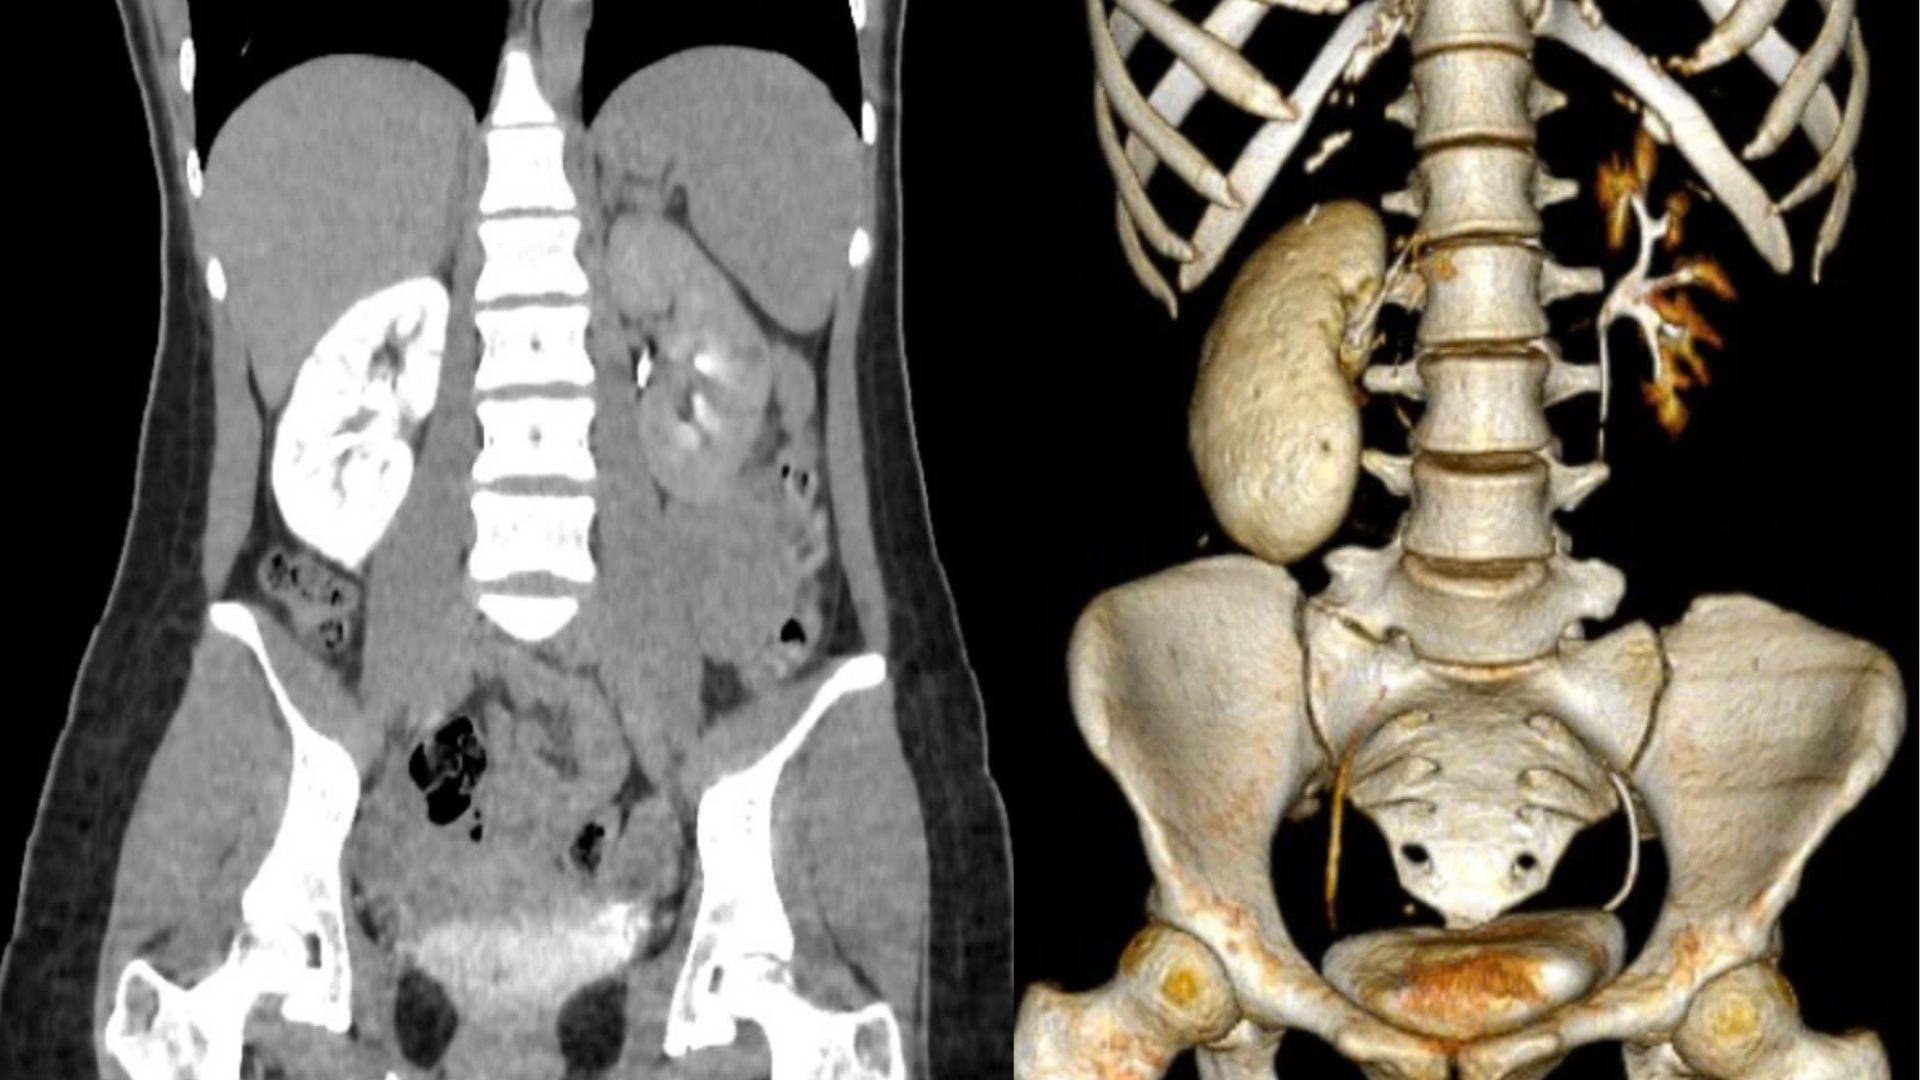

Kết quả thăm khám khiến bác sĩ bất ngờ bởi thận của bệnh nhân bị viêm nặng, xuất hiện nhiều viên sỏi nhỏ. Đặc biệt, một viên sỏi kích thước khoảng 4 mm đã di chuyển và làm tắc nghẽn niệu quản, dẫn đến dòng nước tiểu không thể lưu thông, gây viêm mô thận nặng. "Thận của bệnh nhân gần như bị xơ hóa, cứng lại như hóa đá, mất chức năng hoạt động bình thường", bác sĩ Lực cho biết.

Theo bác sĩ Mai Văn Lực, bệnh lý sỏi thận ở Việt Nam có xu hướng gia tăng, một phần do yếu tố địa lý. Việt Nam thuộc khu vực “vành đai sỏi” – nơi có tỷ lệ mắc sỏi thận cao, ước tính từ 12 – 14% dân số. Ngoài ra, hàng loạt nguyên nhân có thể góp phần hình thành sỏi: dị dạng đường tiết niệu, rối loạn chuyển hóa canxi, thay đổi pH nước tiểu, môi trường làm việc nóng bức, lười uống nước, chế độ ăn mặn hoặc ít vận động…

Người mắc sỏi thận thường có biểu hiện đau vùng hông lưng. Nếu sỏi rơi xuống niệu quản, sẽ gây cơn đau quặn dữ dội, lan từ lưng xuống bụng dưới, kèm tiểu buốt, tiểu rắt. Nếu không điều trị, sỏi có thể làm tắc nghẽn đường tiết niệu, dẫn tới nhiễm trùng hoặc suy thận.